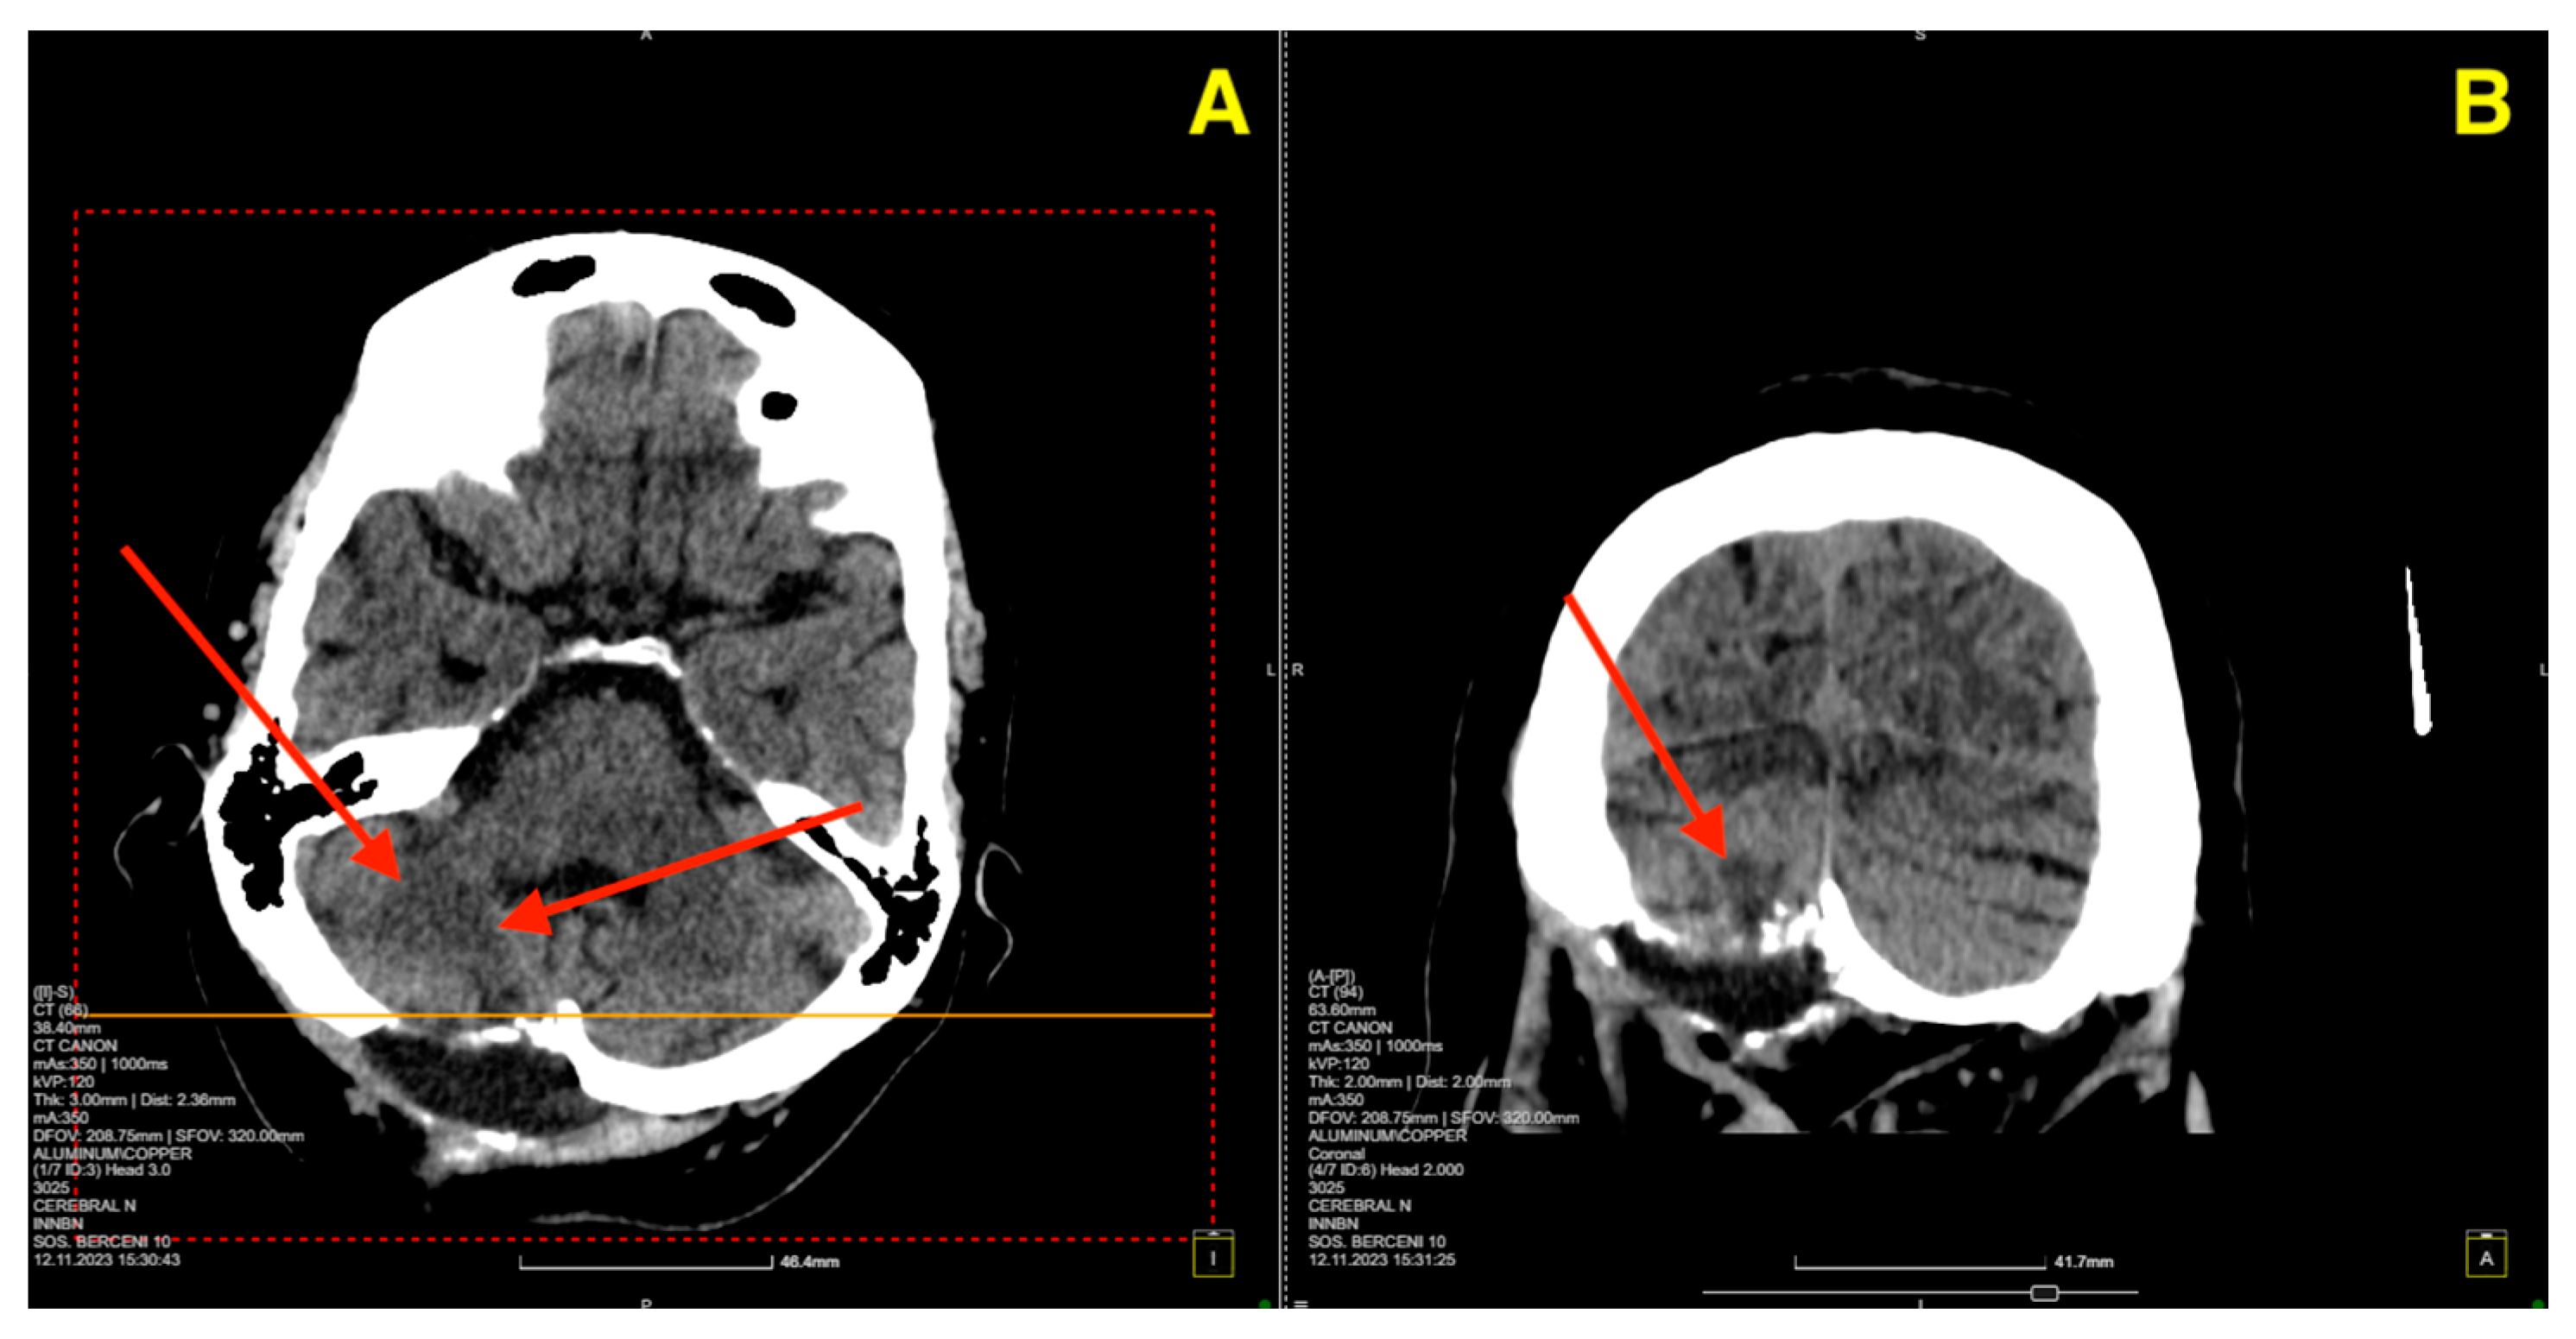

Given the patient’s symptoms and neurological findings, an MRI scan of the brain was performed to further evaluate potential cerebellar or vestibular pathology. The MRI revealed a well-circumscribed cavernous malformation (cavernoma) located in the right cerebellar hemisphere (Figure 1 and Figure 2). The lesion appeared hyperintense on T2-weighted imaging, with a peripheral rim of hemosiderin, suggestive of prior microhemorrhages. The lesion measured approximately 1.5 cm in diameter and was localized to the posterior fossa, without any evidence of acute hemorrhage or mass effect. The surrounding cerebellar structures, including the brainstem, showed no significant compression or deviation. Magnetic resonance angiography (MRA), performed to rule out vascular anomalies, confirmed the absence of arteriovenous malformations or other vascular abnormalities (Figure 1D and Figure 2D). The lesion was determined to be isolated, with no direct involvement of the major cerebellar arteries or veins.

Figure 1. Pre-op MRI scan. (A) (Axial T2-weighted MRI): Displays the lesion in the right cerebellar hemisphere, highlighted by the red arrow, which points to a hyperintense core surrounded by hemosiderin deposition at the periphery, consistent with a cavernous malformation. (B) (Sagittal T2-weighted MRI): The red arrow indicates the location of the lesion in the posterior fossa, situated near the cerebellar hemisphere, without significant impact on the cerebellar vermis or brainstem. (C) (Coronal T2-weighted MRI): The red arrow emphasizes the lesion’s size and well-defined borders relative to the surrounding cerebellar tissue, confirming the absence of surrounding edema. (D) (MRA Axial View): No red arrow is present as this image confirms the absence of any vascular abnormalities in proximity to the lesion.

Figure 2. The red arrow highlights the cerebellar cavernous malformation (CCM) located in the right cerebellar hemisphere. This lesion is characterized by its hypointense signal on T1-weighted MRI images (AC), consistent with prior microhemorrhages and hemosiderin deposition surrounding the malformation. The lesion’s distinct margins and location, without significant mass effect on adjacent structures such as the brainstem and fourth ventricle, are emphasized by the arrow. The MRA (D) further confirms the absence of vascular anomalies, distinguishing the lesion as a solitary cavernoma without associated arteriovenous malformation.